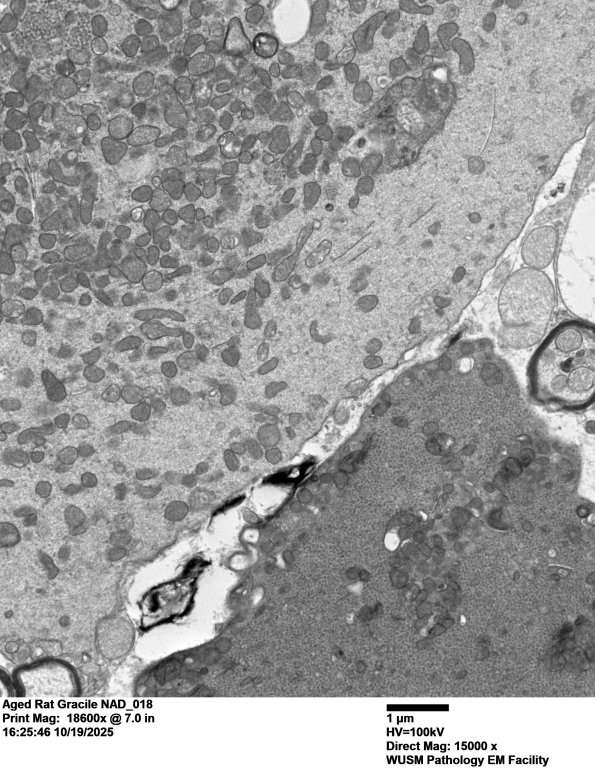

Higher magnification of the two elements of image #18C1 showing their different contents. (electron micrograph)